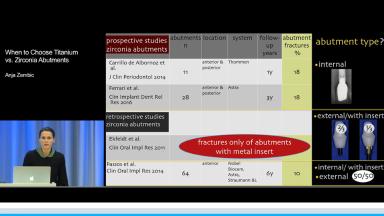

Implant-supported single crowns are a well-established treatment option for the replacement of missing teeth. This lecture will help the clinician to choose between metal and ceramic abutments for the prosthetic treatment phase. Ceramic abutments have gained in popularity with more favorable esthetic outcomes than those provided by metal abutments.

Developments in material science have enhanced the properties of ceramics that are known to be brittle with an increased risk for fractures. This presentation discusses yttria-stabilized tetragonal zirconia polycrystal (Y-TZP), a high-strength ceramic with superior mechanical properties compared to all other ceramics. Y-TZP abutments are examined as an alternative to the well-established titanium abutments. Differences in clinical outcomes using titanium and zirconia abutments based on the present evidence are outlined. In addition, influencing factors for the choice of the abutment material are highlighted to help the clinician to make the ideal choice for different clinical situations.

- highlight differences in clinical outcomes between the two approaches